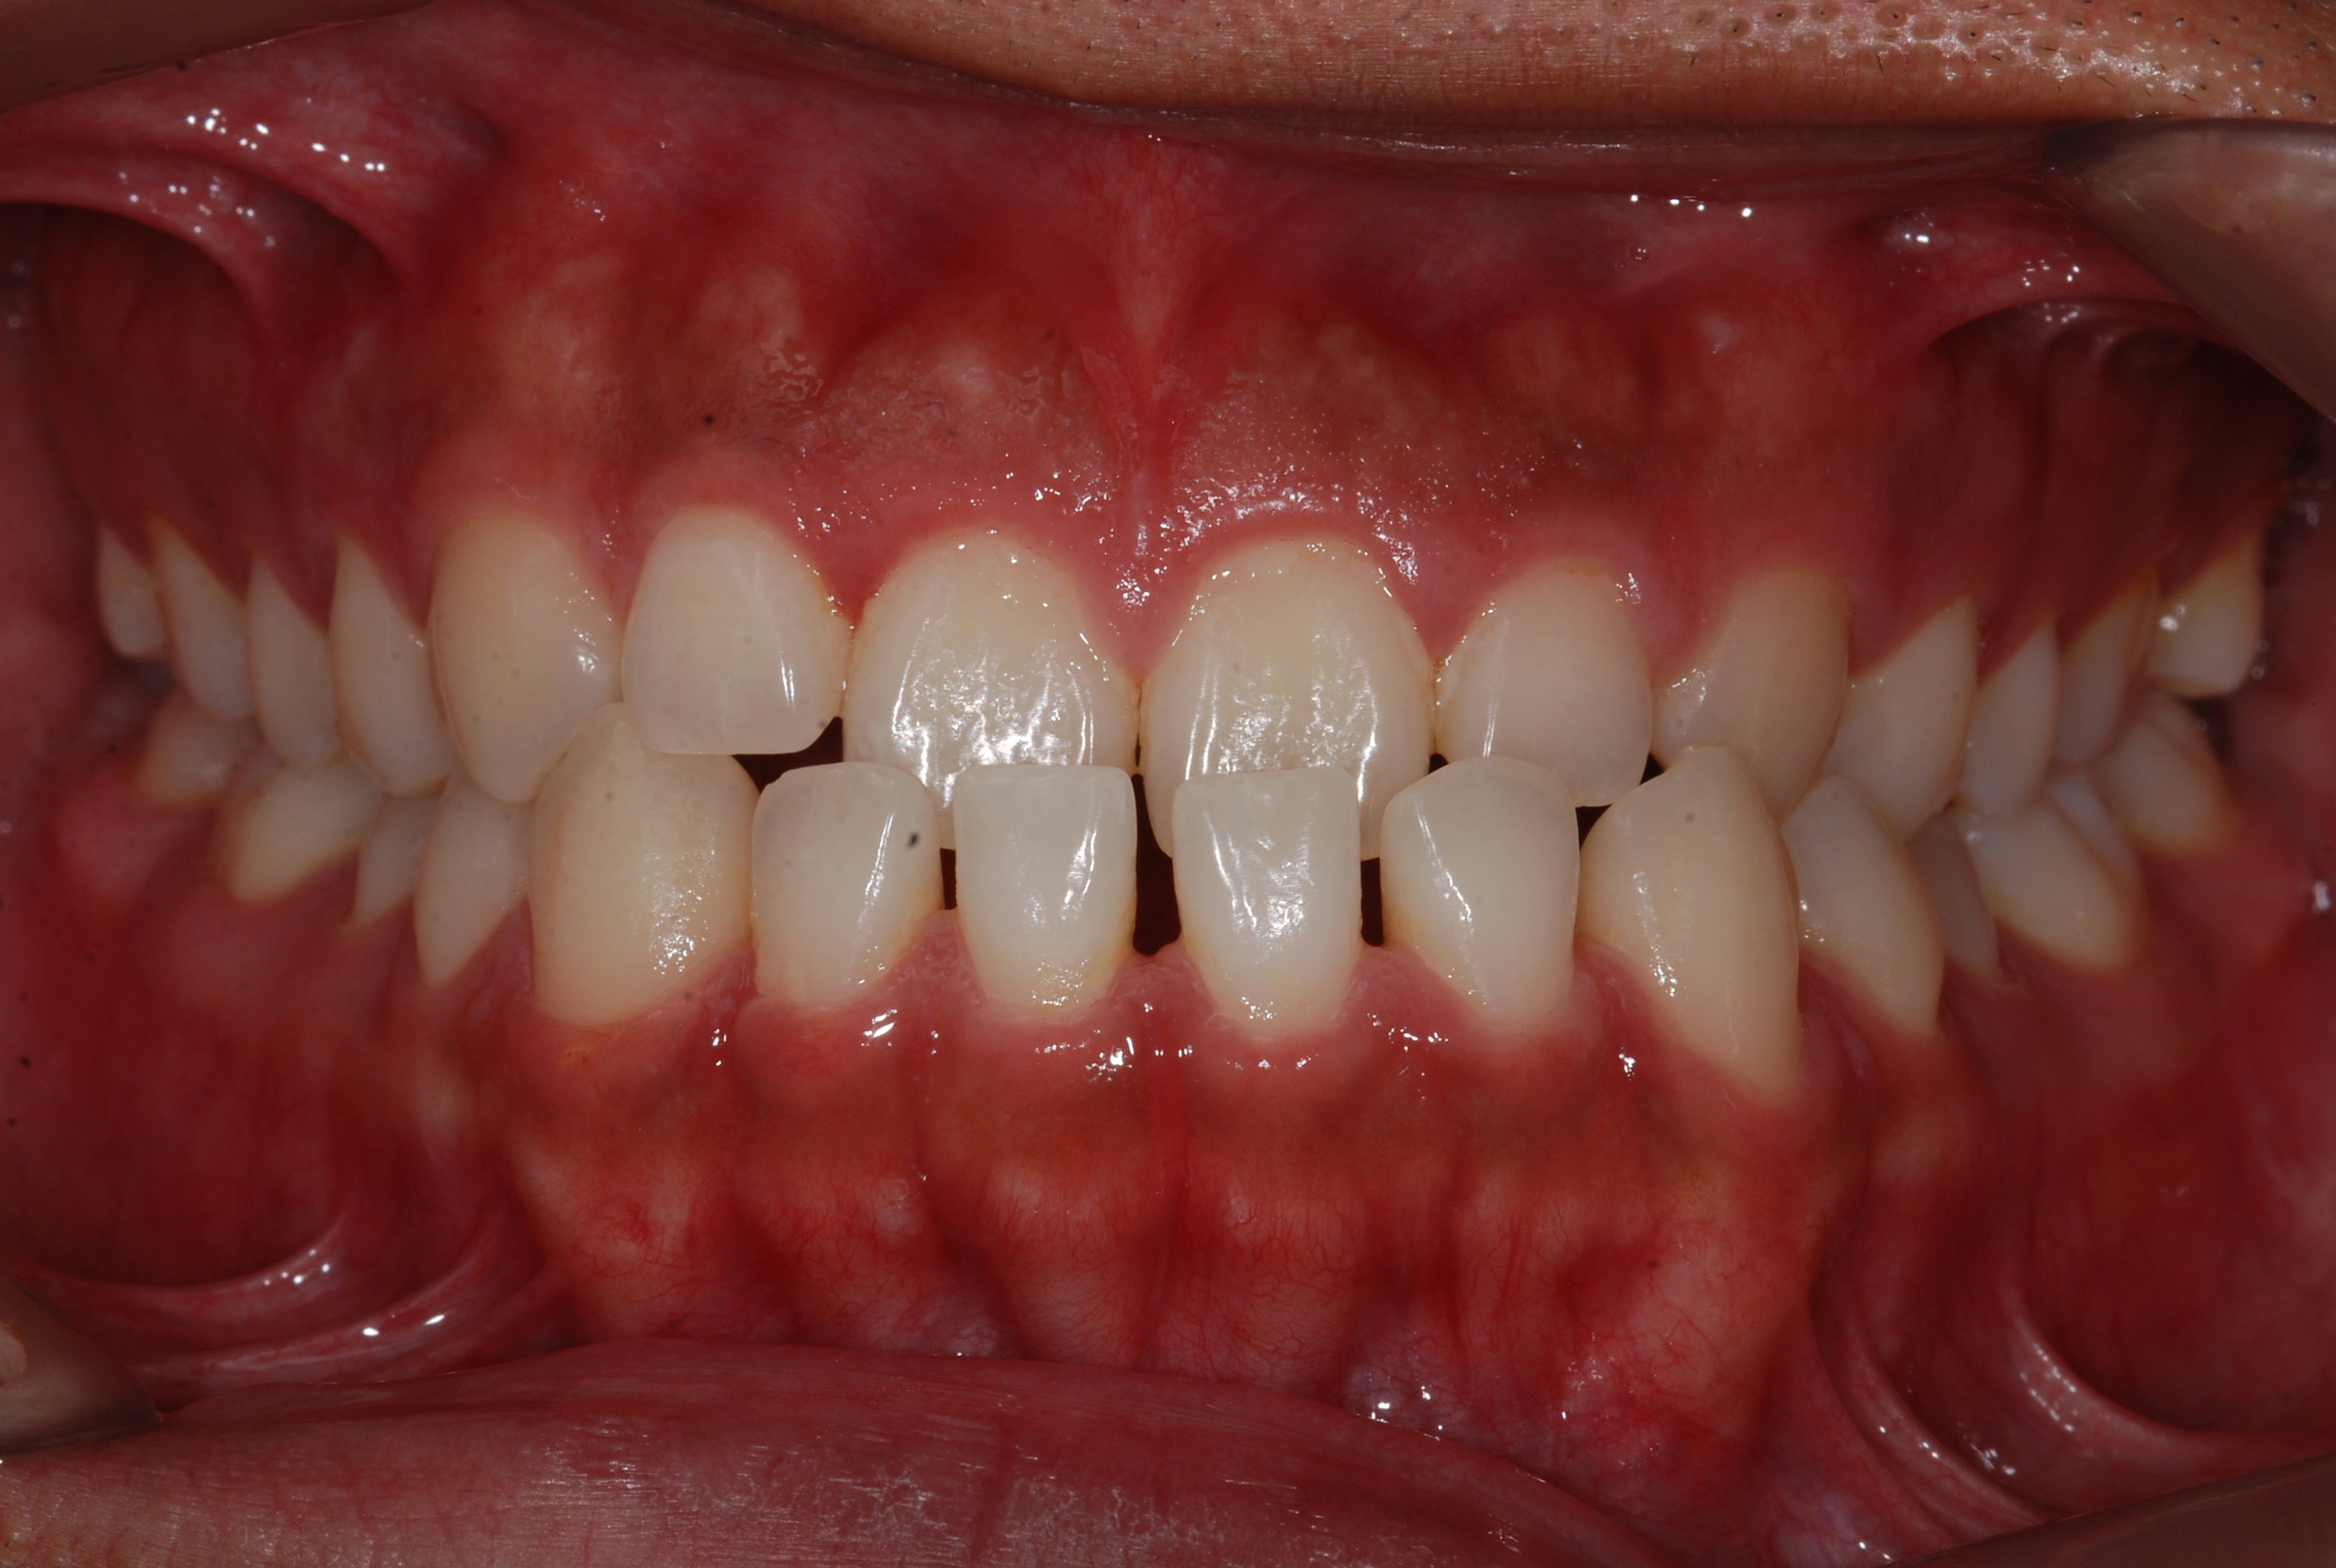

치료 전 사진입니다.